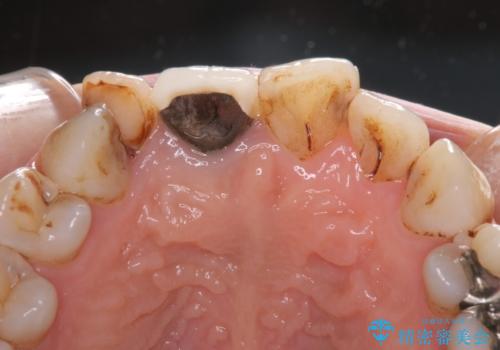

- 前歯の歯並びやむし歯治療の跡、奥歯の銀歯を気にして来院された患者様です。

インビザラインによる矯正治療の後に虫歯や銀歯をセラミックにて補綴することとしました。

前歯のむし歯治療の跡や奥歯の目立つ銀歯がなくなり、明るい口元になりました。